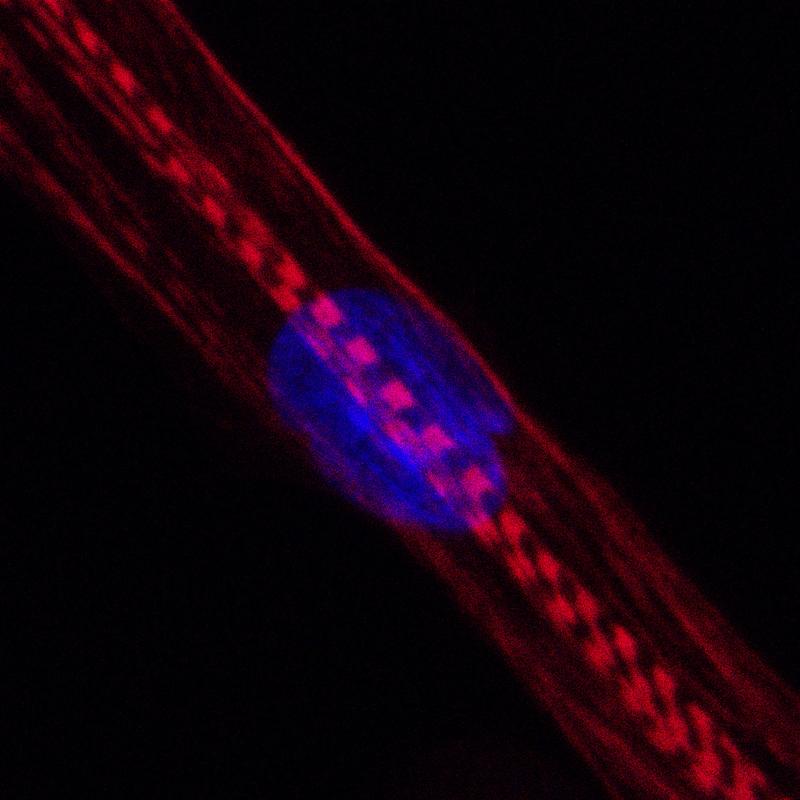

Für ihre Untersuchung setzte die Gruppe um die Erstautorin der Studie, Dr. Stefanie Anke Grunwald von der Muscle Research Unit am ECRC, insgesamt 22 Populationen menschlicher Skelettmuskelzellen jeweils zwei verschiedenen Statinen aus: zum einem dem fettlöslichen Wirkstoff Simvastatin, zum anderen dem wasserlöslichen Wirkstoff Rosuvastatin. Anschließend untersuchten die Forscherinnen und Forscher, welche Gene in den Zellen jeweils angeschaltet waren und in Proteine umgesetzt wurden und welche nicht. Zudem analysierten sie den Stoffwechsel der Zellen und beurteilten ihren Zustand anhand morphologischer Kriterien.

„Die Ergebnisse waren hochinteressant“, sagt Spuler. „Ganz offensichtlich üben Statine in der allgemein üblichen Wirkstoffmenge dramatische strukturelle, funktionelle und metabolische Effekte auf die Muskeln aus.“ Sie und ihr Team stießen in den untersuchten Zellen beispielsweise auf rund 2.500 Gene, die in Anwesenheit der Medikamente anders reguliert wurden als gewöhnlich. Dadurch war die Produktion von mehr als 900 Proteinen verändert: Sie wurden entweder in zu geringen oder zu großen Mengen hergestellt. Der Einfluss von Simvastatin war diesbezüglich höher als der von Rosuvastatin.

„Mithilfe funktioneller Analysen konnten wir bestätigen, dass die Entwicklung, das Wachstum und die Teilung der Skelettmuskelzellen durch die Statine beeinträchtigt werden“, sagt Spuler. Sie und ihr Team fanden einen Weg, um die negativen Effekte der Medikamente etwas einzudämmen: „Die Gabe von Omega-3- oder Omega-6-Fettsäuren machte die Wirkungen von Simvastatin und Rosuvastatin teilweise rückgängig“, berichtet die Wissenschaftlerin. Eine ergänzende Einnahme derartiger Präparate könne daher eine Möglichkeit sein, um einer Statin-Myopathie vorzubeugen oder sie zu behandeln.